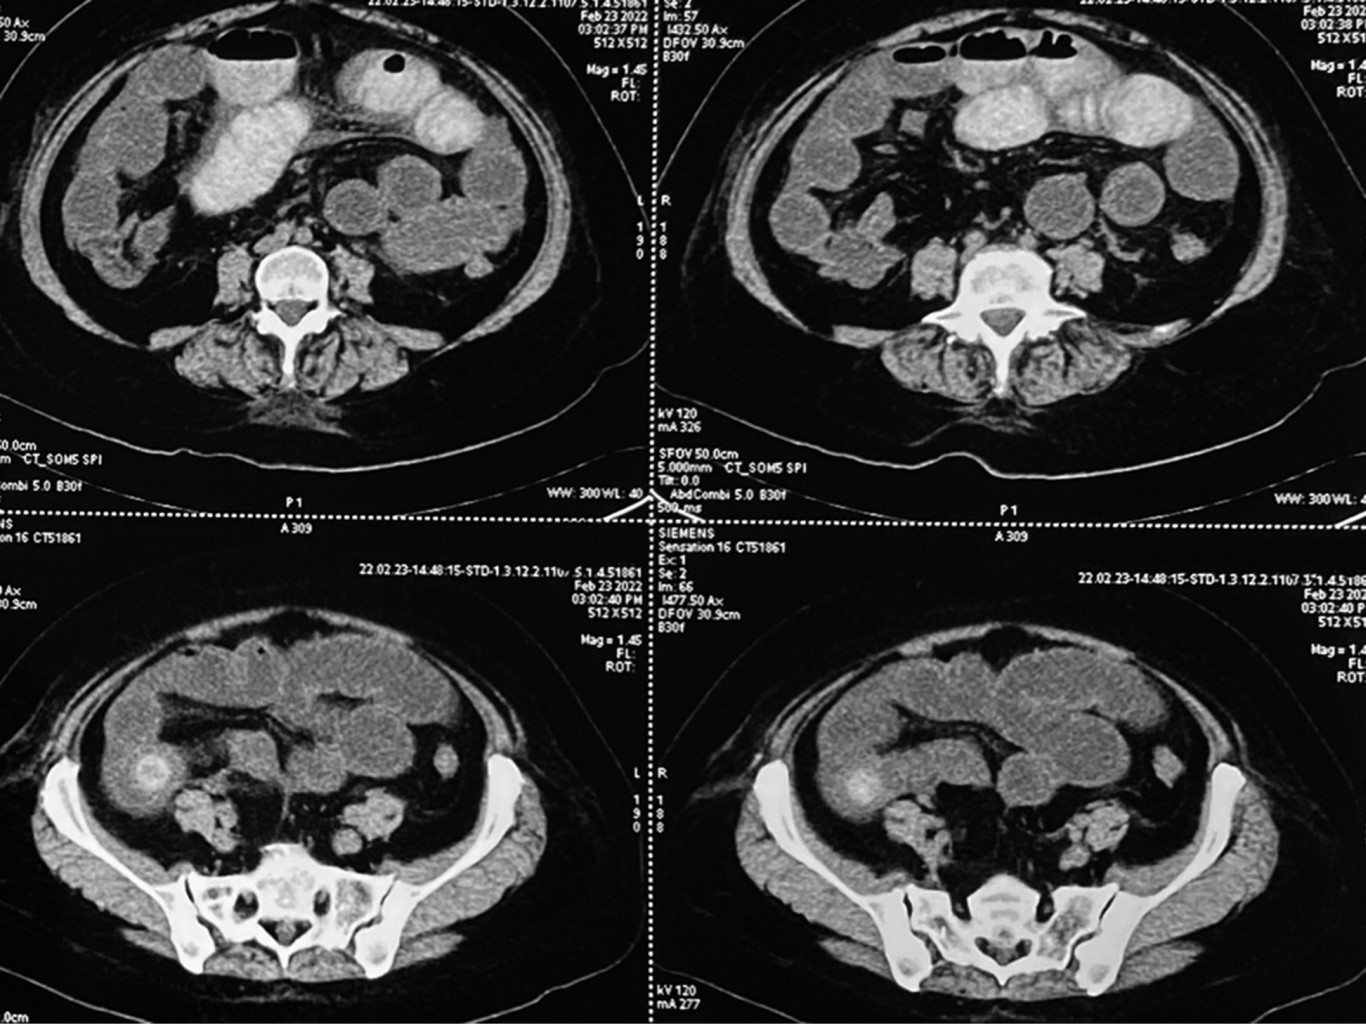

We present the case of a 58-year-old woman from Tequesquitlan, Jalisco, living in Manzanillo, Colima. She came to the emergency department for clinical symptoms of eight days of evolution characterized by pain in the epigastrium 9/10 on the visual analog scale, stabbing type accompanied by nausea that progresses to vomiting of gastrobiliary content, bowel movements, and flatus present. Management with antacids was initiated by a private physician prior to admission to the emergency room without improvement of symptoms. Physical examination showed relevant findings of abdominal distension with pain on superficial and deep palpation located in the epigastrium and mesogastrium, generalized tympanic movement, and decreased peristalsis. No muscle resistance or peritoneal irritation was found at the time of admission. She is allergic to dextromethorphan and penicillin. She denies any history of abdominal pain suggestive of cholecystitis. Chronic degenerative diseases and surgeries were also denied. Her lab tests showed white blood cells 18.13 × 103/milliliters, with neutrophils 15.56 × 103/milliliters, lymphocytes 1.44 × 103/milliliters, hemoglobin 11.60 grams/deciliters, hematocrit 34.60%, platelets 359 × 103/milliliters, creatinine 0.60 milligrams/deciliters, urea nitrogen 8.6 milligrams/deciliters, urea 18.5 milligrams/deciliters, sodium 138 mEq/l, potassium 3.3 mEq/l, and chlorine 104 mEq/l. A computed axial tomography scan with oral contrast material was performed, finding gallbladder with contrast material coming from duodenum showing anomalous communication between both structures concerning a fistulous tract at the level of the second portion of duodenum, bowel loops associated to multiple hydro-aerial levels secondary to a 24 millimeters litho in the distal ileum at 40 centimeters from the ileocecal valve with distention of loops proximal to this site (Figure 1). A nasogastric tube was placed on the first day of hospital admission with an output of 1,400 cubic centimeters in the first 24 hours.

Biliary ileus is a rare complication of vesicular lithiasis corresponding to 0.3-0.4%; the most frequent mechanism of a litho passage is through a vesicular-duodenal fistula, the same situation presented by our patient. This clinical case of biliary ileus corresponds to an unusual presentation since the age of the case is below 65 years, which corresponds to less than 4% of the incidence of this pathology, according to the literature cited in this publication. A calculus larger than 2 cm in diameter generates obstruction at the small bowel level in 90% of the cases,2 in agreement with ours, where a 24 mm stone was documented by computed axial tomography (CAT) scan and was responsible for the occlusive picture at the beginning of the disease; however, the spontaneous expulsion of the stone in the feces stands out. The few documented cases of spontaneous expulsion of the stone in the biliary ileus are worth noting, which makes our case report an infrequent resolution of the biliary ileus. Only eight cases of 112 cases with spontaneous resolution have been reported in the Japanese literature. There is still controversy about the management of biliary ileus. However, most of the literature agrees that surgical management remains the treatment of choice in all reported cases, recommending enterolithotomy with stone extraction, followed by cholecystectomy and fistula repair. In this case, a single-stage surgery was performed since it offers the advantages of avoiding future complications, such as gallbladder carcinoma in 15%, cholecystitis or cholangitis, or recurrence of obstructive symptoms.6

Establishing an early diagnosis of biliary ileus helps us prevent complications secondary to an obstructive condition at the intestinal level using imaging studies. The best study will always be a computerized tomography scan reinforced with contrast material because it has a sensitivity over 90% compared to other studies. The treatment will always be surgical and mainly aimed at resolving the obstruction with an enterotomy and extraction of the calculus. Subsequently, the bilioenteric fistula causing the arrival of the stone to the intestinal lumen will have to be repaired to prevent subsequent cases of biliary ileus and reduce the risk of biliary vesicular cancer secondary to the reflux of gastrointestinal contents into the gallbladder through this communication.

Figure 1